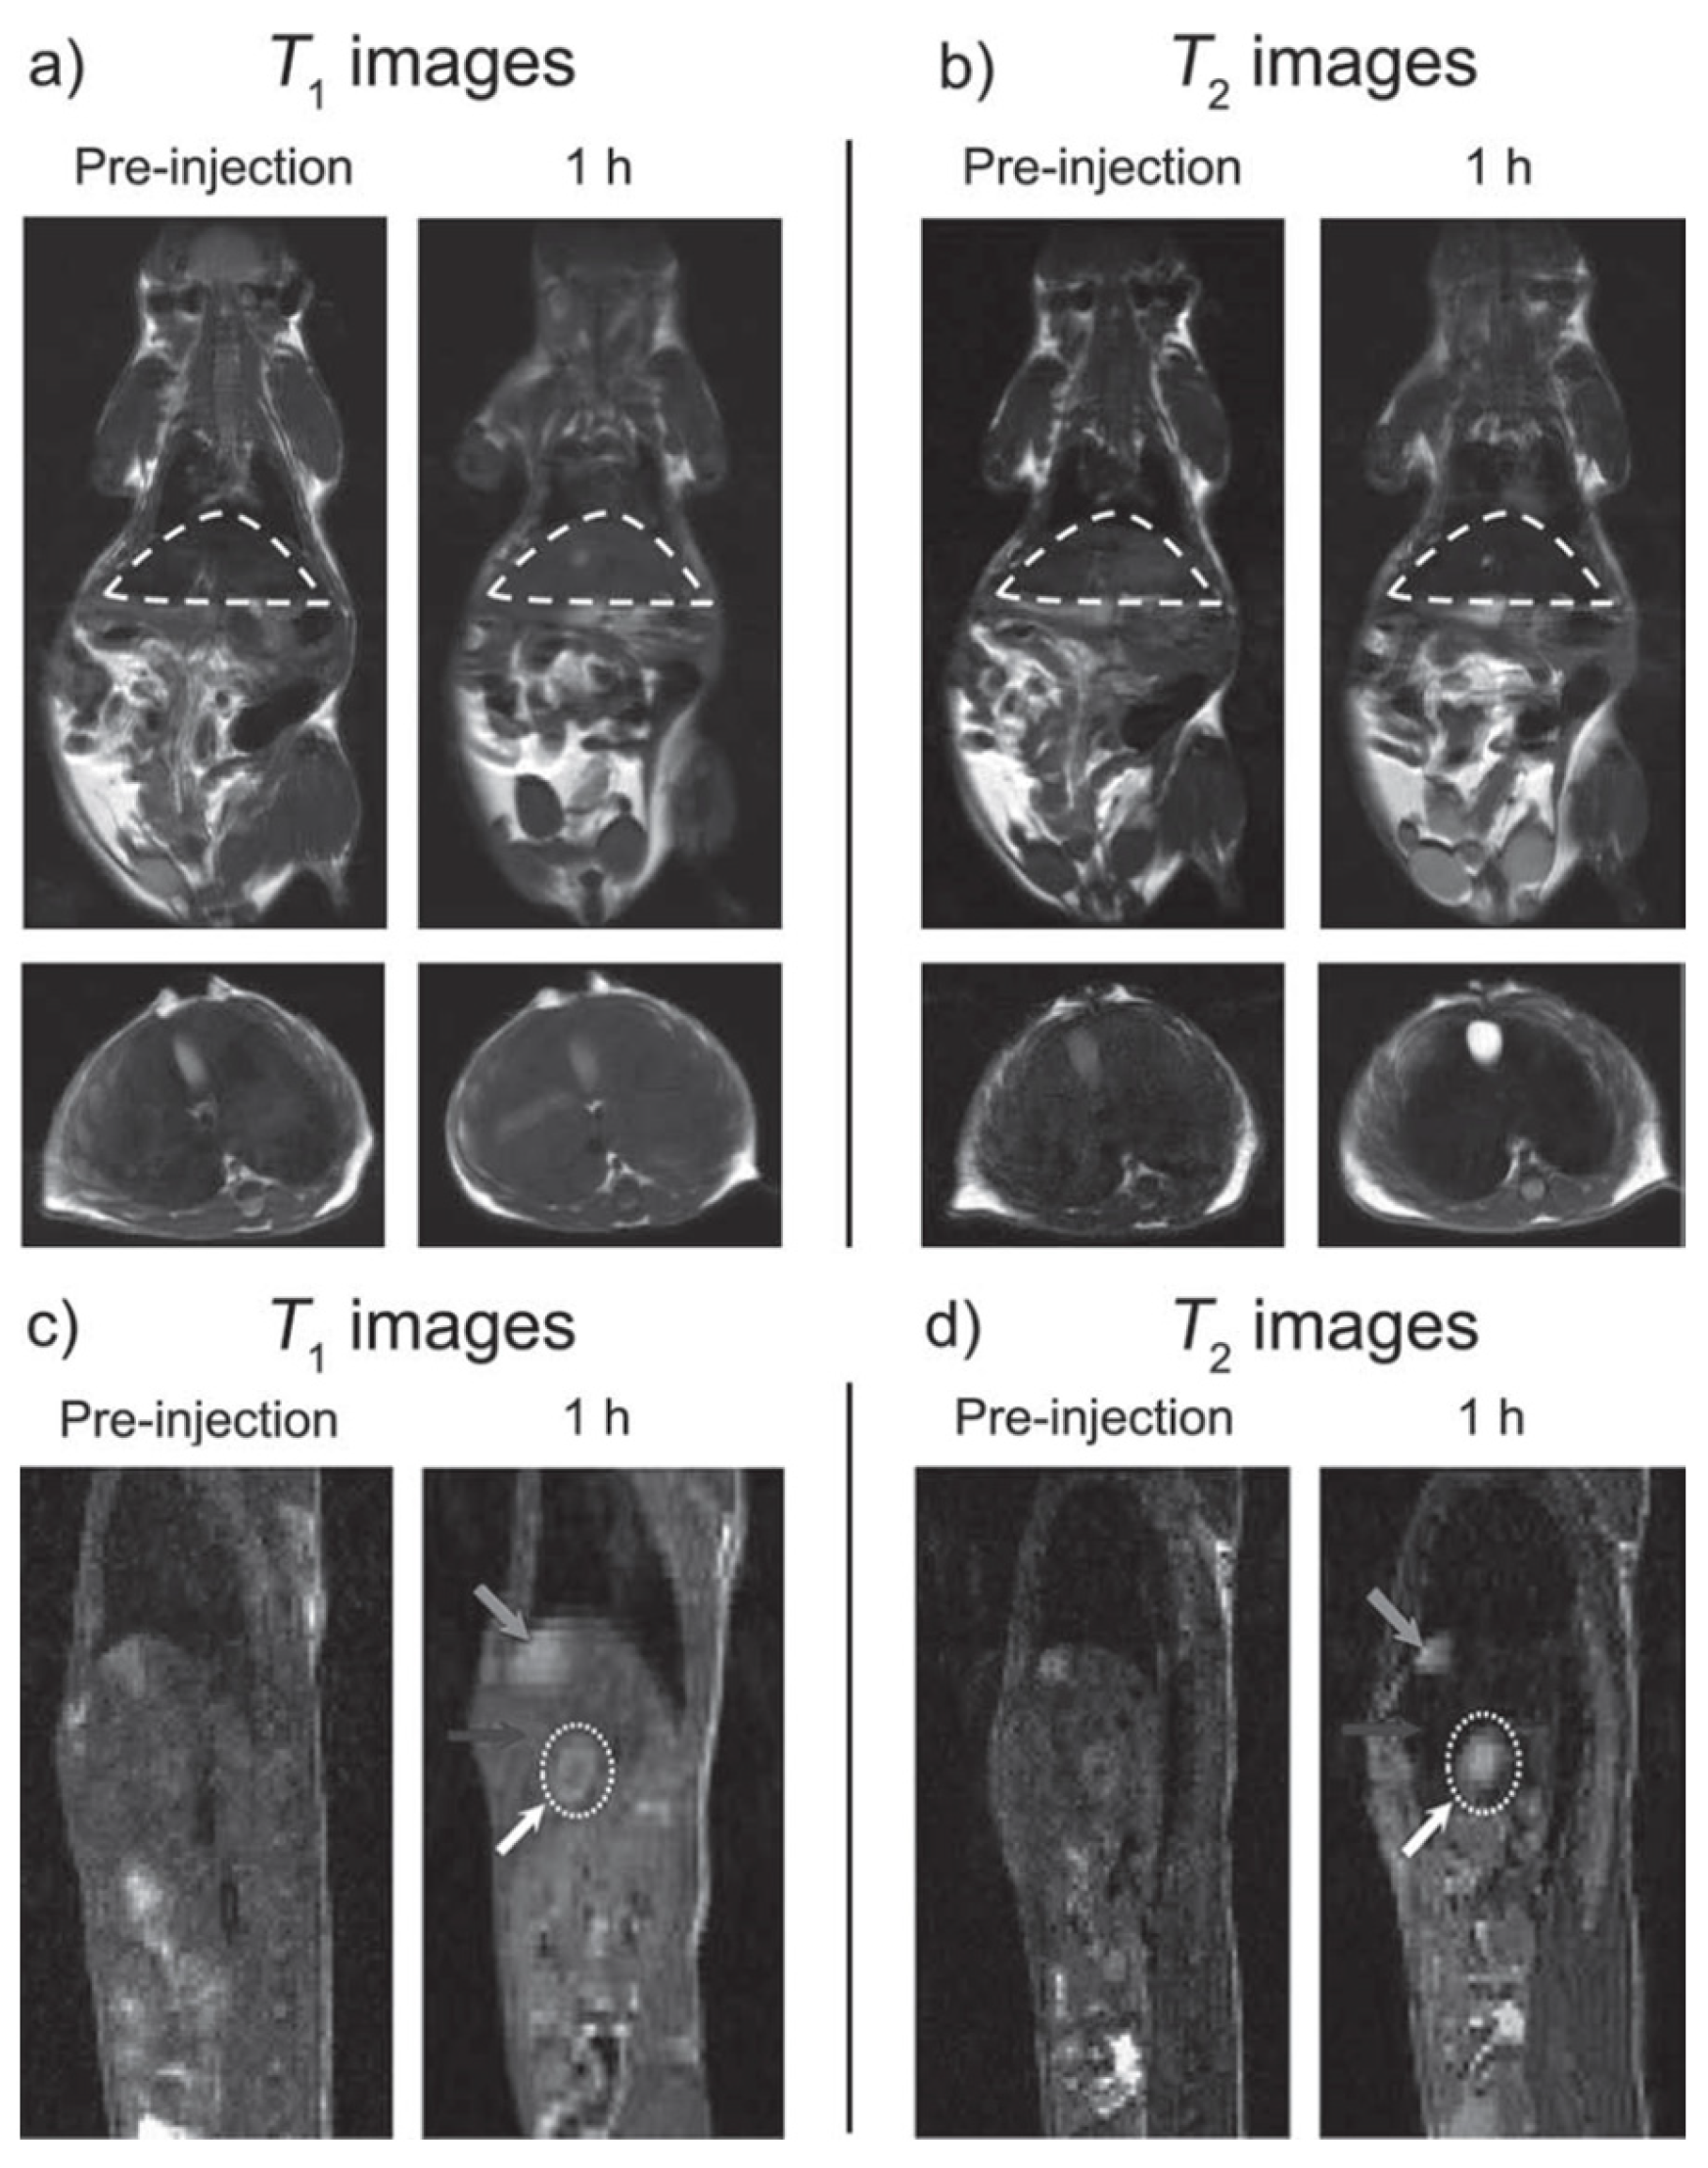

- Im, G.H.; Kim, S.M.; Lee, D.-G.; Lee, W.J.; Lee, J.H.; Lee, I.S. Fe3O4/MnO hybrid nanocrystals as a dual contrast agent for both T1- and T2-weighted liver MRI. Biomaterials 2013, 34, 2069–2076. [Google Scholar] [CrossRef] [PubMed]